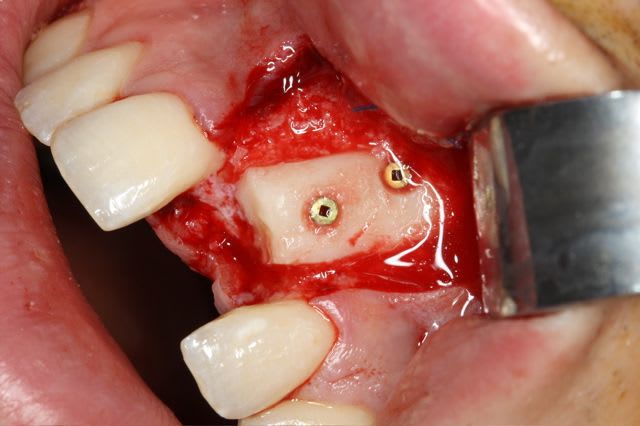

greffe onaly,

dépose des vis et pose de l'implant à 5mois1/2 avec un cj roulé et mise en place de la vis de cica,

pour la greffe: un lit de copeaux généreux et un bloc corticale par dessus et des copeaux pour boucher les espaces. Pas de membrane par dessus, seulement le périoste.